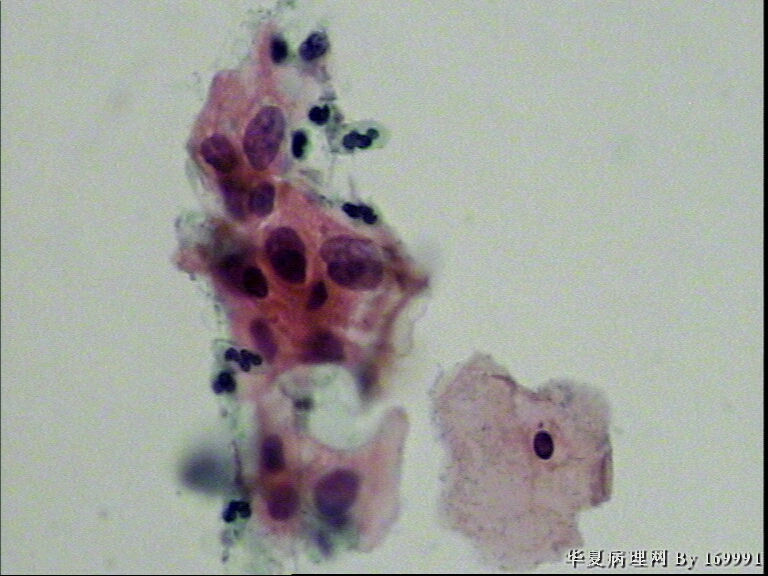

宫颈液基,患者35岁

asc-h

低级别

asc-us